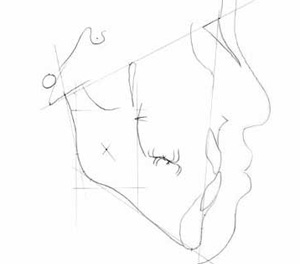

トレースの施行

レントゲンフィルムを正確にトレースします。

トレース図

この図には計測ポイントが定められており、距離や角度を計測するのに用いられます。それらの計測項目は性別や年齢に応じてあらかじめ正常値と正常範囲が判っているので、それらと比較することで、患者様の骨格や歯の位置や方向が、正常に対してどんな相違があるかを知ることができます。 具体的にはコンピュータを用いて専用のソフトで線形角度分析を行い正常値との比較を行い、以下のポリゴン表とプロフィログラムを作成します。当院では市販のソフトではなく、大学勤務時代に独自に開発した分析ソフトを用いています。